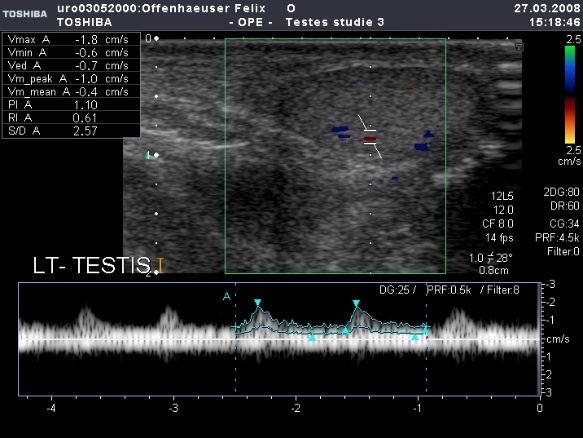

Die Problematik bei der Hodensonographie liegt in den erschwerten Schallbedingungen. Zum einen verlaufen im Hoden die zarten arteriellen und venösen Gefäßbahnen in enger Nachbarschaft und werden beim Farbdoppler oft zeitgleich abgeleitet. Dadurch ist die arterielle Flusskurve stets von der venösen überlagert. Darüber hinaus ist der Hoden ein sog. low-flow,/low-resistance Organ. Gerade beim Säuglings- und Kleinkindhoden bedeutet dies arterielle Flussgeschwindigkeiten unter 4 cm/sec. (low-flow) sowie einen erniedrigten Gefäßwiderstand (Resistance Index RI 0,56), bedingt durch eine breite diastolische und eine flache systolische Amplitude. Dadurch ist die Verwendung von hochfrequenten Linearschallköpfen von mind. 12 MHz unabdingbar. Nur mit Hilfe einer hochauflösenden Ultraschallsonde gelingt es den intratestikulären Blutfluss zu detektieren und aussagekräftige Informationen über die Durchblutungsverhältnisse im Hoden zu erhalten.

Während sich mit zunehmendem Alter die Flussgeschwindigkeit in den intratestikulären Gefäßen erhöht, bleibt der Gefäßwiderstand stabil.